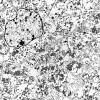

8I1 Granular Cell GBM (Case 8) EM 017 - Copy